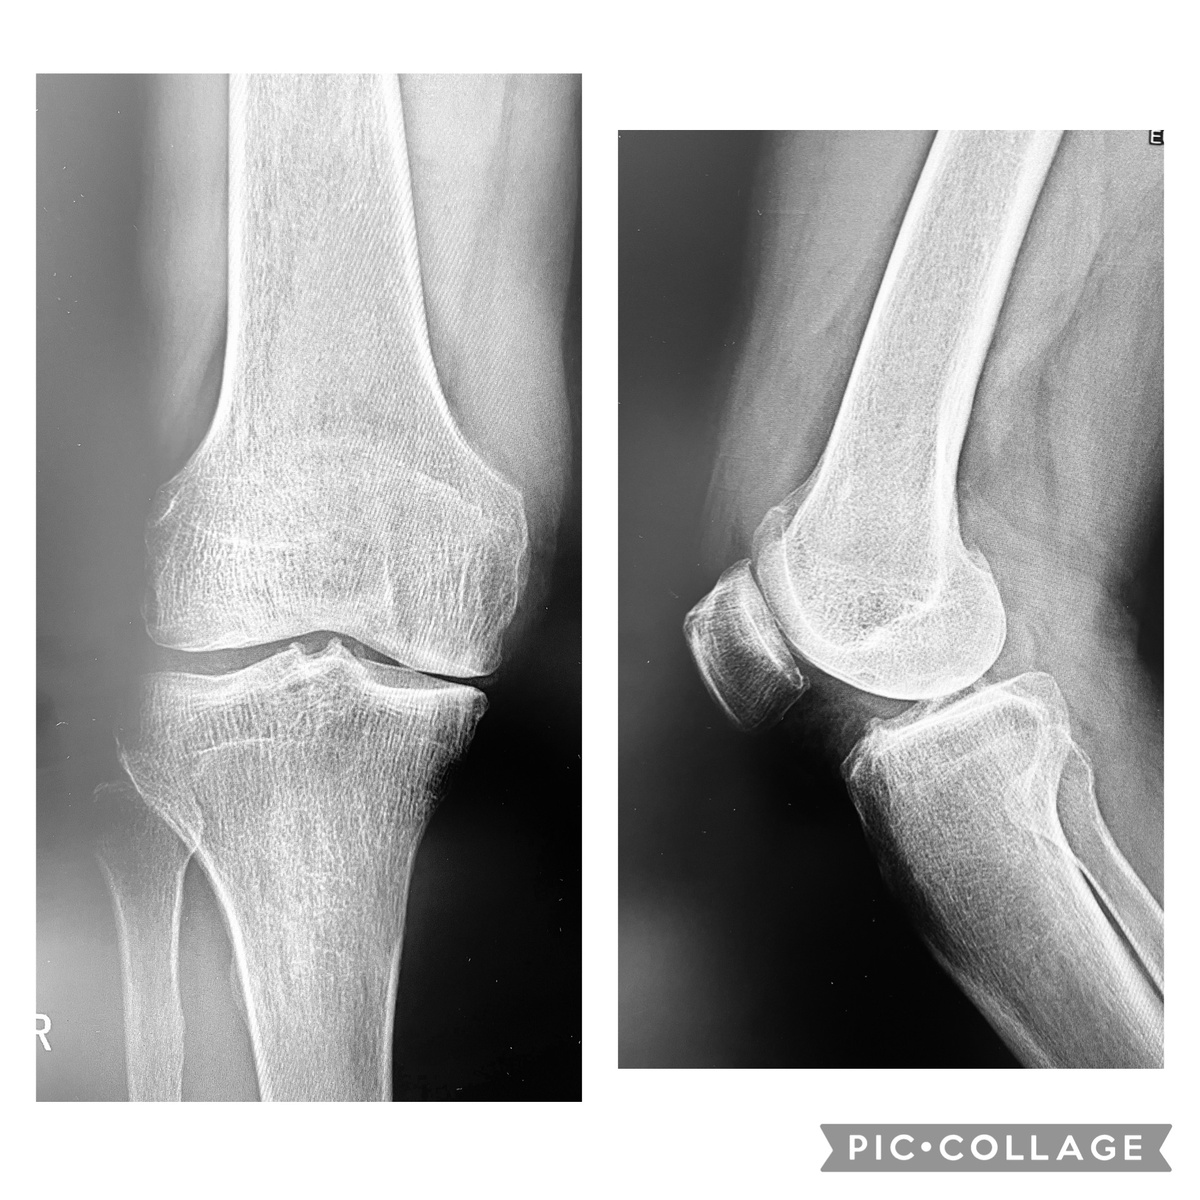

Вполне приличная рентгенограмма. Потому что не артроз.

Пациенту 67 лет. Активный, подвижный, без лишнего веса. Около 10 лет назад повредил медиальный мениск, и жил с этим. Потом появились боли. Инъекции всякого разного в сустав, физиопроцедуры, всё по классике и по высшему разряду. Эффекта почти ноль, пришлось удалить оторванную часть мениска (пару лет назад). На тот момент хрящ бедра выглядел измученным, но еще живым.

Рентгенограмма с нагрузкой очень приличная, колено пока не под протез. Казалось бы - что делать? Протез- рано, а всё остальное не помогает. Тупик? Нет.